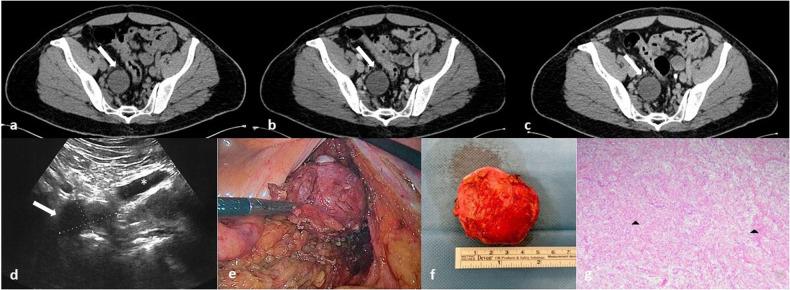

Benign nerve sheath tumors presenting as solitary retroperitoneal masses (RBNSTs) pose a complex diagnostic challenge for multidisciplinary teams regarding differential diagnosis, staging, and treatment planning. This article reviews the role played by different imaging techniques in assessing RBNSTs and elucidates their typical pathological features with a particular emphasis on the correlation between imaging and histological findings. Furthermore, some examples of retroperitoneal tumors that merit consideration in the process of differential diagnosis based on cross-sectional investigations (CSIs) are reported. The correlation between tissue architecture and appearance on imaging can help increase the accuracy of differential diagnosis with other retroperitoneal neoplasms at CSIs.

This educational review critically examines the correlation between imaging and histological features in solitary retroperitoneal benign nerve sheath tumors, offering valuable insights for improving the accuracy of differential diagnosis in clinical radiology.

RBNSTs are challenging to diagnose because they lack specific radiological features. Differential diagnosis of RBNSTs from other retroperitoneal neoplasms on imaging is complex. Surgical removal of RBNSTs is recommended for an accurate diagnosis.